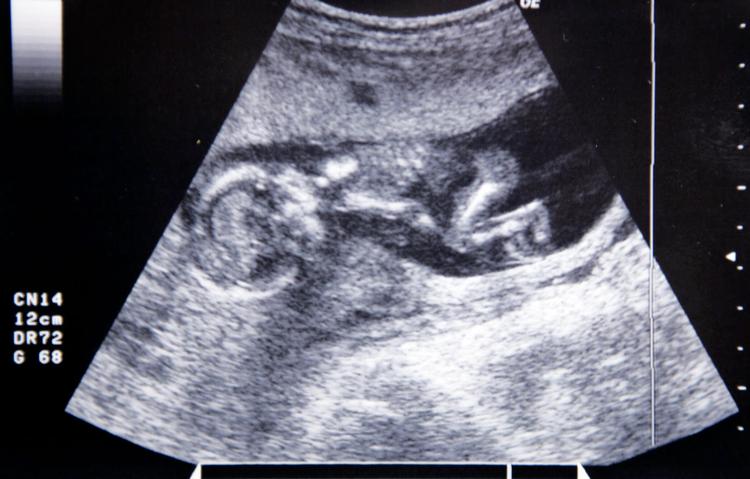

Det moderne menneskes hyldest til menneskerettighederne må betegnes som hykleri, hvis ikke rettighederne gælder for alle - også for det befrugtede æg. Det er et centralt argument i en ny underskriftindsamling, som en række abortmodstandere har taget initiativ til, og som skal få EU-systemet til skrive »retten til liv fra undfangelsen« ind i EU-lovgivningen og forbyde enhver finansiering af aktiviteter, »der har med destruktion af menneskeligt liv at gøre«.

Dermed skal det befrugtede æg anerkendes, som ’One of us’, som er initiativets slogan. Indsamlingen er et såkaldt borgerinitiativ, hvor borgere fra syv EU-lande, der i løbet af et år kan indsamle en million underskrifter, kan tvinge kommissionen til at tage stilling til et forslag. Håber på ny bevidsthed Initiativtagerne kommer fra lande som Italien, Spanien og Polen; i Danmark er det foreningen Retten til Liv, der står for underskriftindsamlingen. Foreningen arbejder på et kristeligt grundlag imod fri abort og er mest kendt som ejer af den omdiskuterede abortmindelund i Vestjylland. »Jeg håber, at vi får vækket en bevidsthed i Europa om det massive angreb mod menneskeligt liv, der foregår i livmoren. Vi ser i USA, at der er meget større bevidsthed om det ufødte barn, abortproblematikken og forskning i menneskelige stamceller«, siger landssekretær Ellen Højlund Wibe. Hun er deltidsansat i foreningen, der har 2.700 medlemmer.